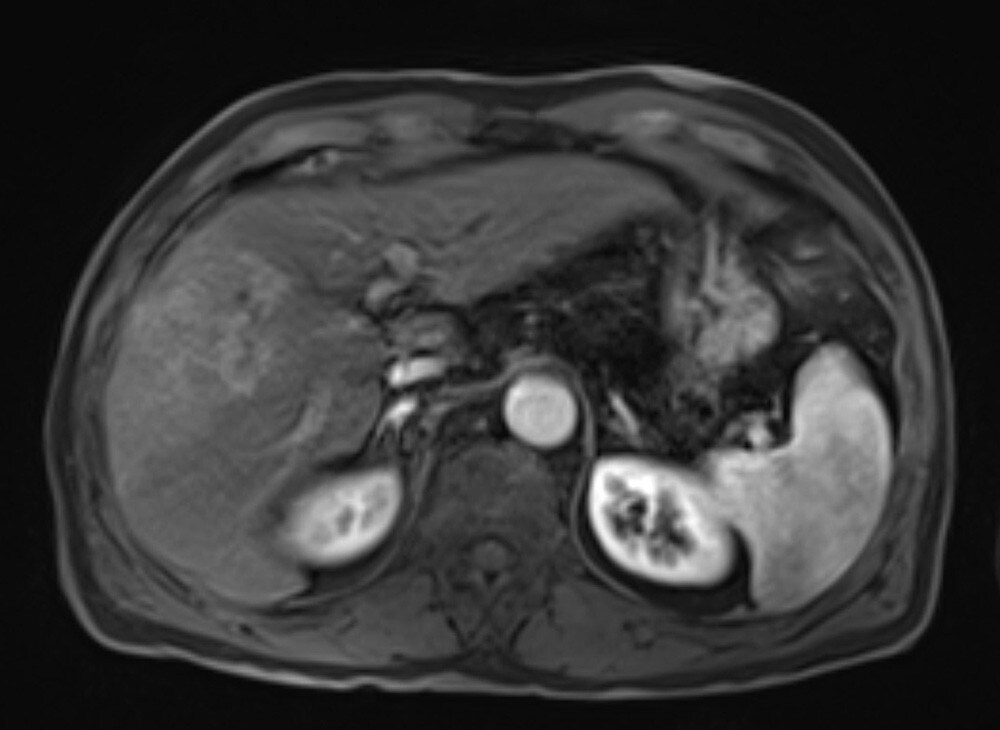

60歳代、男性、57kg、肝細胞癌

前医よりB型慢性肝炎に対して核酸アナログ投与し定期フォローを継続されていた.AFP上昇,腹部USでの画像異常を指摘され精査加療目的に当院紹介受診となり,EOB-MRIを施行した.

EOB-MRIの結果から門脈本幹までの腫瘍栓を伴う肝細胞癌と診断した.EOB-MRI肝細胞相で不均一高信号を呈する病変ではなく,均一低信号を呈しており複合免疫療法が奏効する可能性があると考えられた.Vp4の門脈腫瘍栓を伴う切除不能進行肝癌に対し複合免疫療法(Atezolizumab/Bevacizumab併用療法)を開始した.4コース終了後には門脈腫瘍栓一部残存を認めるも肝腫瘤は著明に縮小し,5コース終了後に根治切除術(肝右葉切除術+門脈血栓除去術)を施行した.術後は薬物療法の再開なく現在までの約14ヶ月無再発で経過観察継続中である.

本症例におけるEOB・プリモビスト造影MRIの役割について

EOB-MRIで門脈腫瘍栓を伴う肝細胞癌であること,不均一高信号を呈する病変で無いことを確認し複合免疫療法(Atezolizumab/Bevacizumab併用療法)を開始した.EOB-MRI肝細胞相は肝細胞癌におけるWnt/βカテニン変異のイメージングバイオマーカーとなることが知られており(Ueno A et al. J Hepatol 61:1080-1087,2014),不均一高信号な病変は複合免疫療法の治療効果が乏しい可能性が指摘されている(Sasaki et al. Cancers,14,827,2022).必ずしも治療奏効を保障するものでは無いが,本症例では肝細胞相で均一低信号を呈しており,複合免疫療法の治療効果が期待される症例であった.